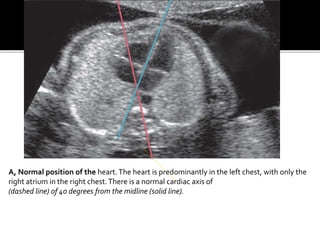

A, Normal position of the heart.The heart is predominantly in the left chest, with only the

right atrium in the right chest.There is a normal cardiac axis of

(dashed line) of 40 degrees from the midline (solid line).

A, Normal positionof the heart.The heart is predominantly in the left chest, with only the right atrium in the right chest.There is a normal cardiac axis of (dashed line) of 40 degrees from the midline (solid line).